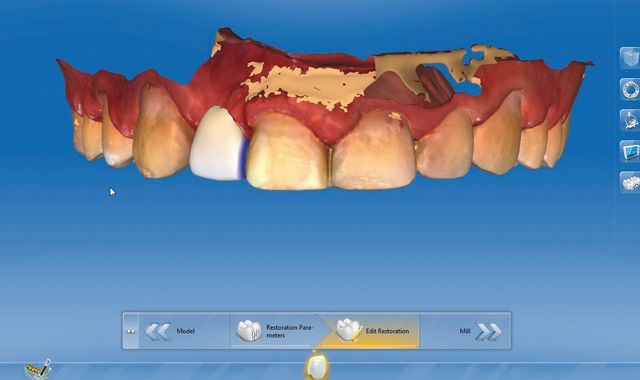

Fig. 15 The lab then trimmed the digital model for the design of the implant surgical guide directly in the software.

Fig. 16 Parameters were set for specific fit and thickness of the surgical guide.

Fig. 17 Sleeve and design tools for the surgical guide are also available to the inLab SW 15 technician.

Fig. 18 An automatic proposal of the surgical guide was then displayed in the inLab SW 15 with various tools available to modify the design (i.e. addition, removal and integration of viewing windows).